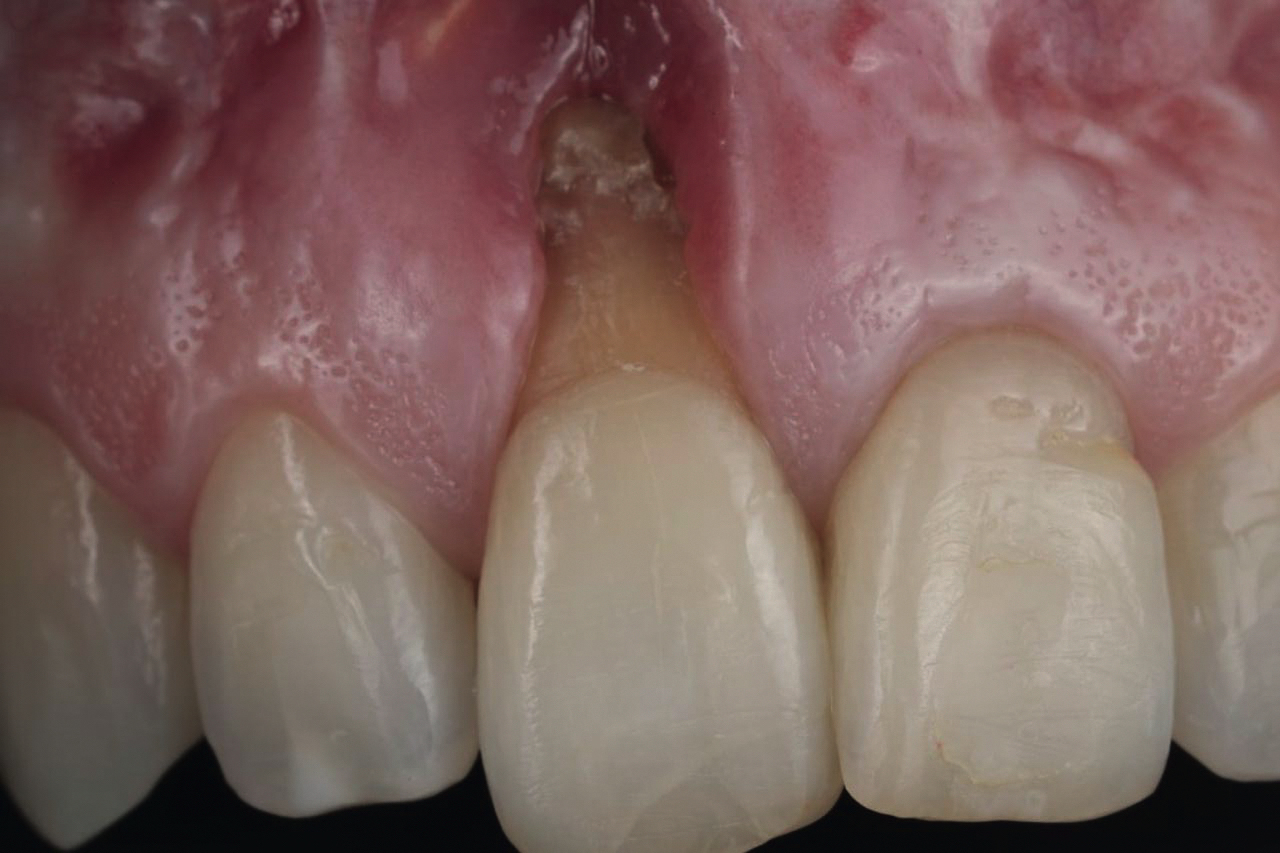

• Рецессии десны: причины и диагностика

• Устранение рецессий: анкетирование

• Хирургические методы устранения рецессий

• Пластика мягких тканей в области имплантатов